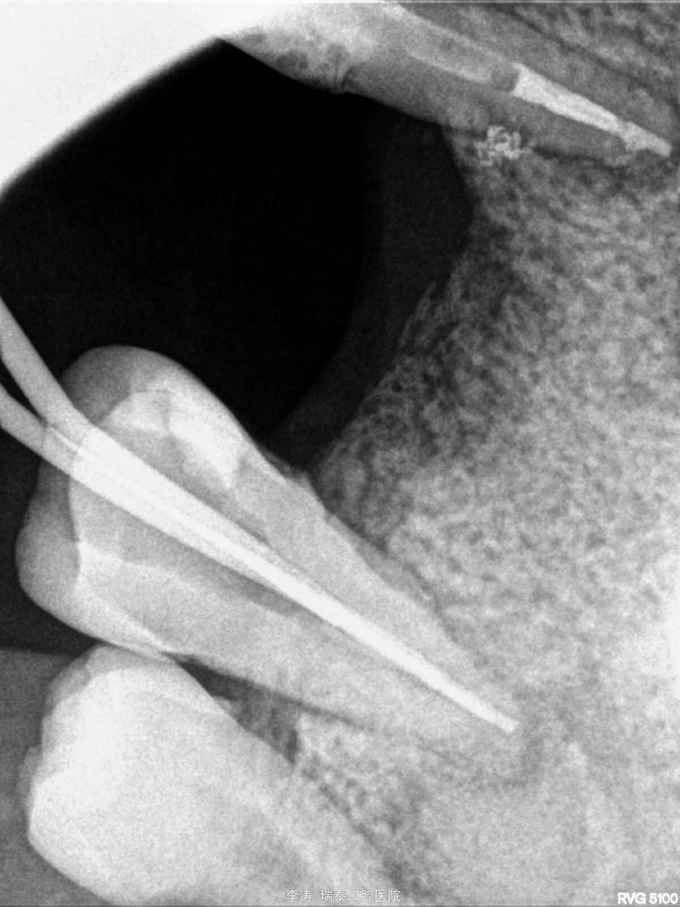

根尖区病变牙的治疗一例

牙骨质瘤 牙骨质瘤

26残冠 25,27根管治疗不到位 27牙根尖区高密度影 所有牙均无临床症状

经多方会诊,确认考虑27牙根尖牙骨质瘤,建议先行根管治疗,然后密切观察 予以拔除26,根管治疗25,27